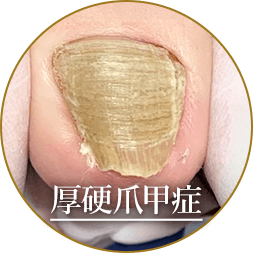

爪が分厚かったり変形している場合は、爪の機能が衰えてしまっている状態です。

原因は様々ですが一度機能が衰えてしまうと、時間が経っても元の正常な爪には残念ながら戻りません。